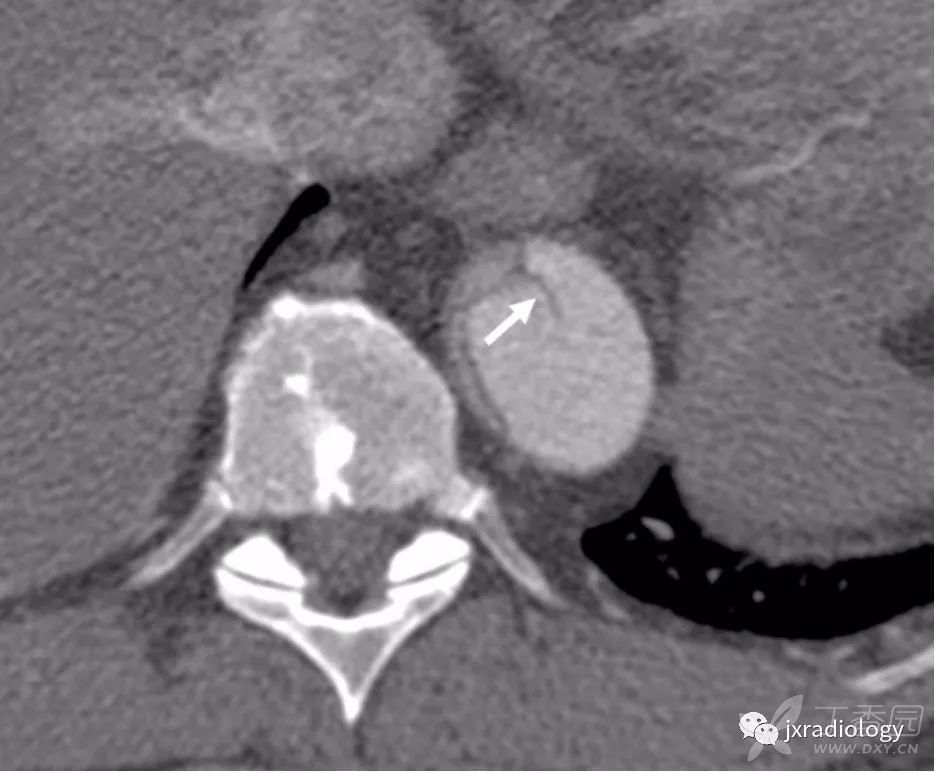

平扫CT上显示广泛的动脉粥样硬化通常是PAU患者的一个特征。注射对比剂后,主动脉壁出现不规则边缘和围绕溃疡基底部的内膜钙化提示PAU诊断( 图13 )。

图13:在轴位非增强CT显示主动脉后壁广泛的动脉粥样硬化(a图中箭头)。注射对比剂后,没有内膜瓣的情况下主动脉的后囊袋状突起(b和c图的星号)。

当发生破裂时,很难区分破裂的是动脉瘤或复杂的动脉粥样硬化性溃疡。在这两种情况下,都需要立即进行手术治疗。非穿透性溃疡一般限于内膜并常常无症状( 图14 )。